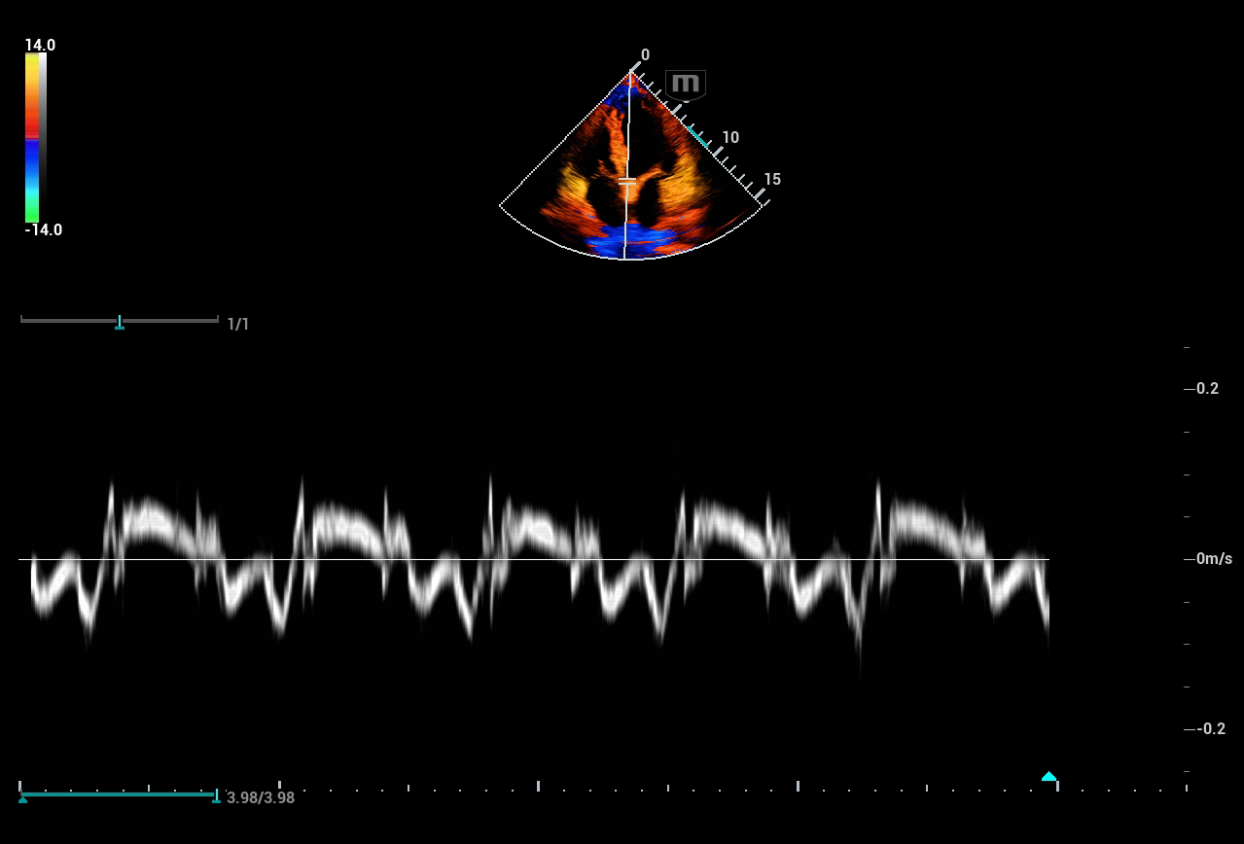

Consona presenta soluzioni nuove e concrete, che aiutano a effettuare diagnosi efficaci con semplicitĂ , rivolgendosi a un'ampia platea di pazienti. La serie mette a disposizione strumenti estremamente avanzati per rimanere all'avanguardia nella diagnosi cardiovascolare.

Galleria di immagini